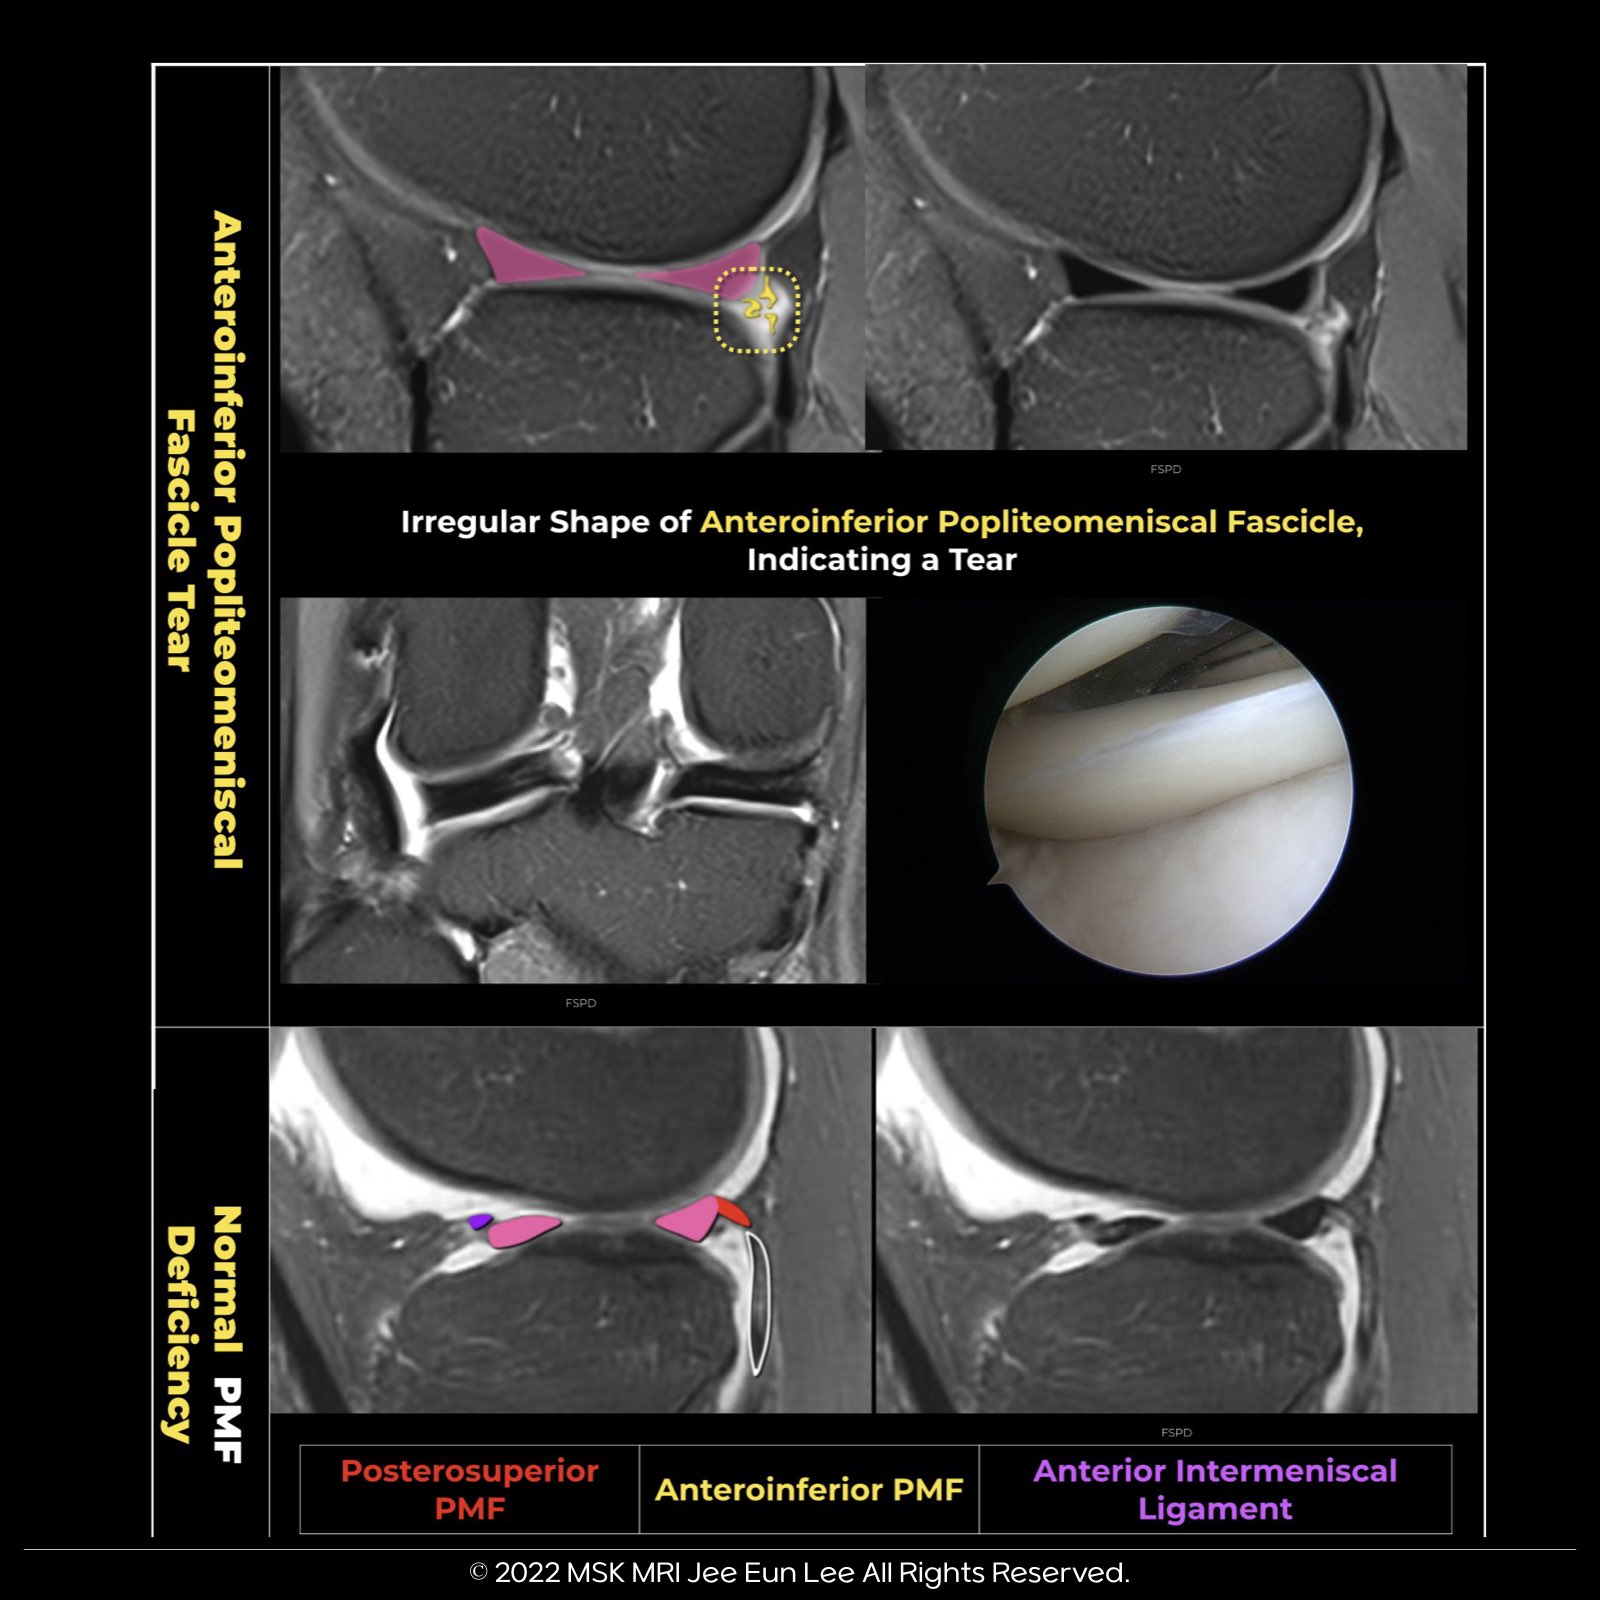

🔵🇰🇷Normal popliteomeniscal fascicle deficiencies

- The normal absence of the anteroinferior popliteomeniscal fascicle allows the popliteus tendon to traverse from the lateral to the medial side through the hiatus.

- A slice further medially through the hiatus reveals this normal deficiency of the fascicle.